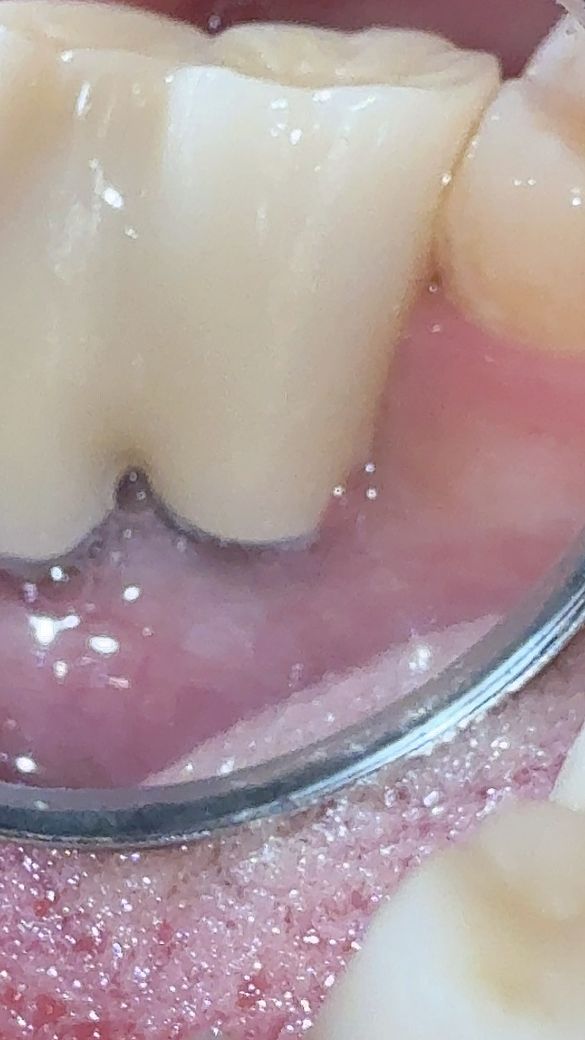

임플란트 보철물 주변의 잇몸에 관련하여 문의드립니다

임플란트 후 관리차원에서 치간칫솔과 워터픽을 사용하고 있긴합니다만 그래서 그런건지 주위염이 발생한건지 첨부된 사진에 체크한곳이

평소랑은 다르게 보철물 위로 잇몸살이 덮힌건지 부은건지 뭔가 보여서요

• 1번 째 사진